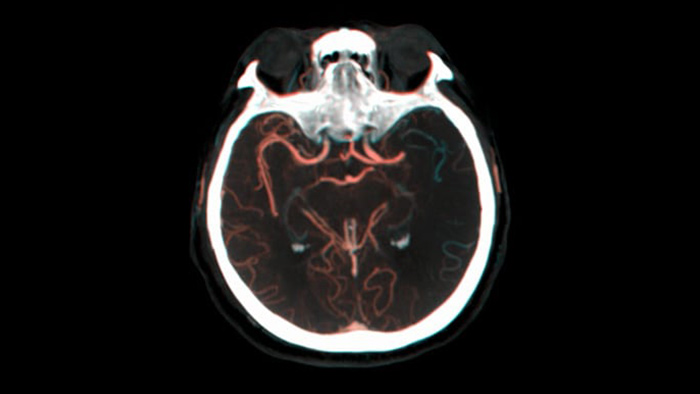

Ver la repleción colateral

Visualización de la repleción colateral

Dual View permite visualizar  los volúmenes de TAC de haz cónico de fase temprana y tardía yuxtapuestos mejorando la identificación de penumbra y la visualización de la repleción colateral.